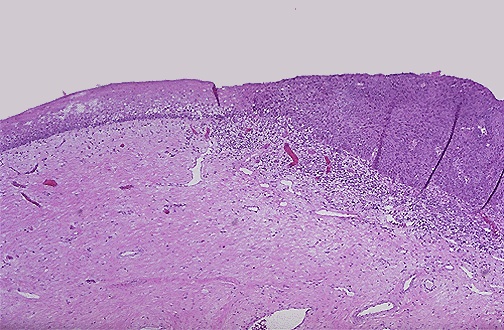

| The normal cervical squamous epithelium at the left transforms to dysplastic epithelium on the right. There is also underlying chronic inflammation because abnormal epithelial surface does not provide the same protective barrier as normal epithelial surfaces do. |